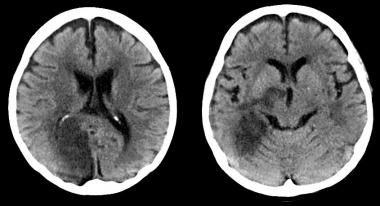

En un subestudio del SPRINT se encuentra que los niveles más bajos de presión arterial se asociaron a una pequeña disminución de lesiones de la sustancia blanca, de significación clínica incierta. JAMA 13 de agosto de 2019

En 30 años de seguimiento de una cohorte británica, el consumo de 2 a 3 bebidas alcohólicas por día se asoció con lesiones en la resonancia magnética cerebral y peores resultados en las pruebas de lenguaje. BMJ, 6 de junio de 2017